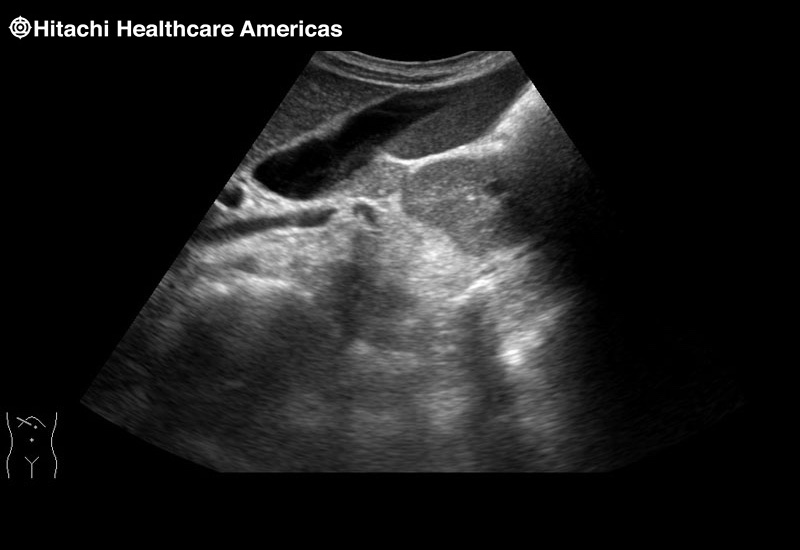

Giving the surgeon complete control

The Fujifilm Healthcare transducer utilizes the full benefits of the Wrist Articulation™ of the robotic instruments to capture real-time ultrasound imaging even at complex angles and difficult-to-reach areas.

The next level in Robotic Ultrasound

Full wrist articulation with optimized functional length.

A critical function of robotic ultrasound guidance is tumor margin identification. Fujifilm's family of robotic probes all have the optimum location of the attaching mechanism that allows for full wrist articulation of the probe. The result is an increased confidence that the tumor margins have been completely identified.